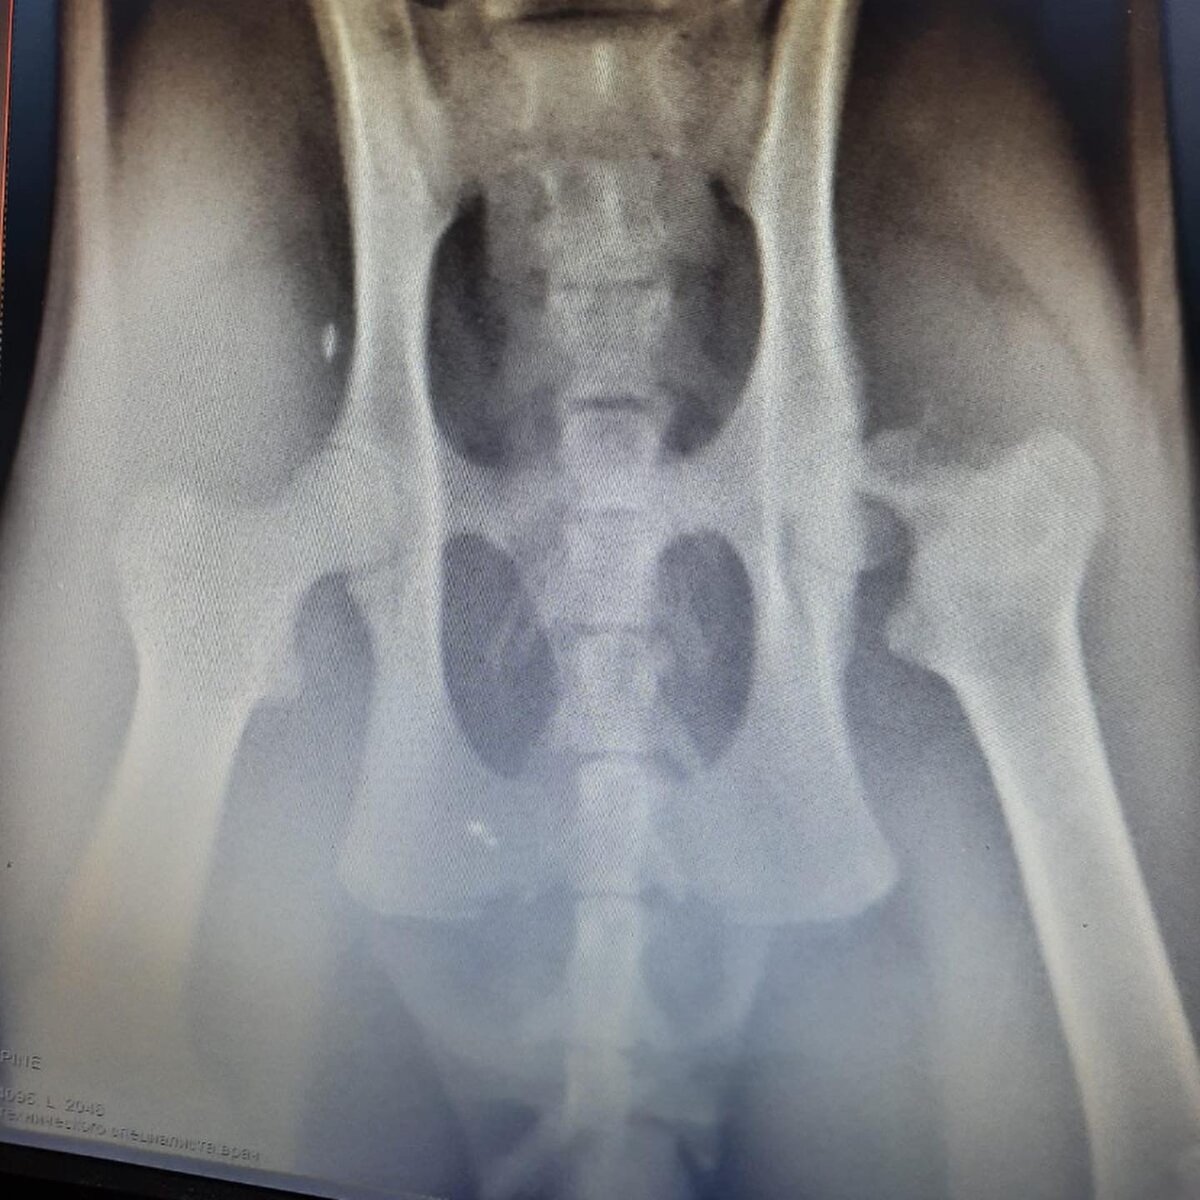

Неравнодушная решилась на кураторство, сдали анализы, перевезли на передержку, а он так и хромает... Обследовали... нужно 25000р на операцию...это перелом шейки бедра...